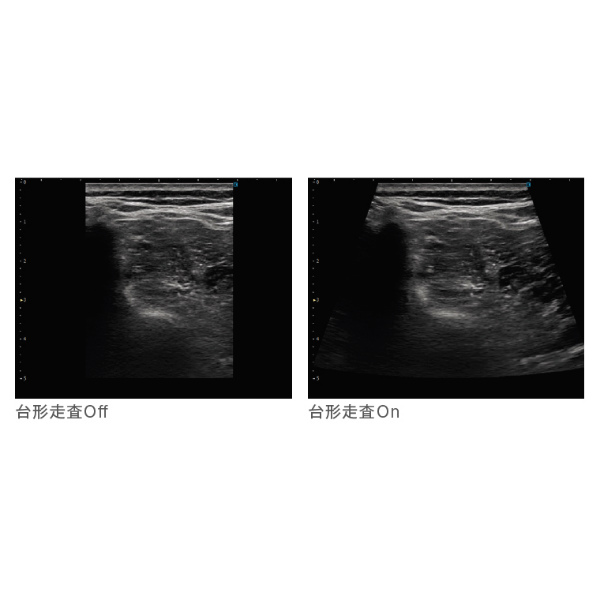

●高い分解能と深度を両立 T2HI®(Triad Tissue Harmonic Imaging)